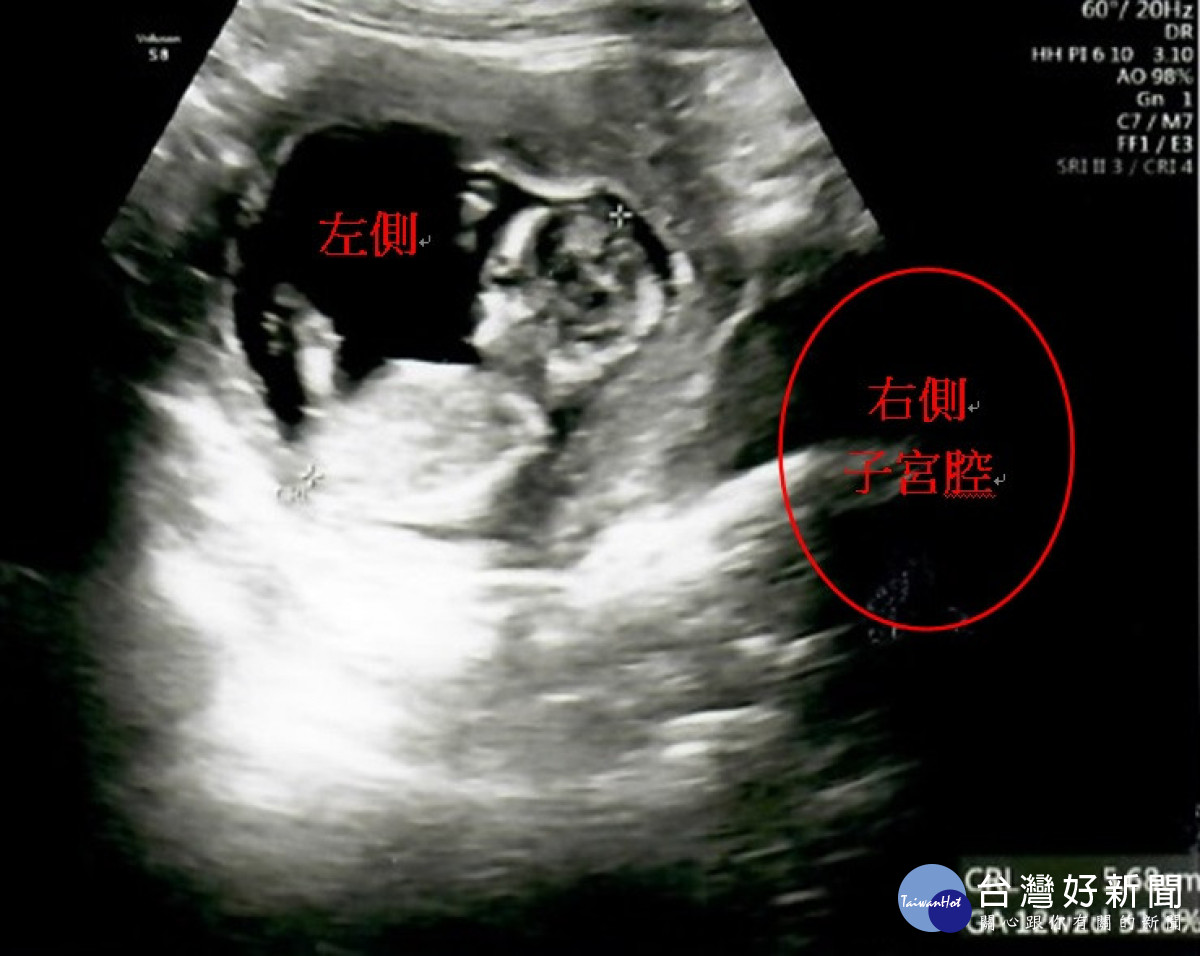

王小姐透過AI人工智慧選取囊胎後成功將囊胎植入右側子宮。曾雪蒨攝

接著醫療團隊幫王小姐進行第1次取卵手術,首次共取出9顆卵子,在受精後得到3顆囊胚,經過「AI人工智慧試管技術」、「胚胎影像即時監控系統(T/L)」(註1),從中找出發育最好的囊胚植入右側的子宮腔內,囊胚也順利著床發育,直到孕期34週又2天時,陳小姐自然產下重達2460公克的健康男寶。